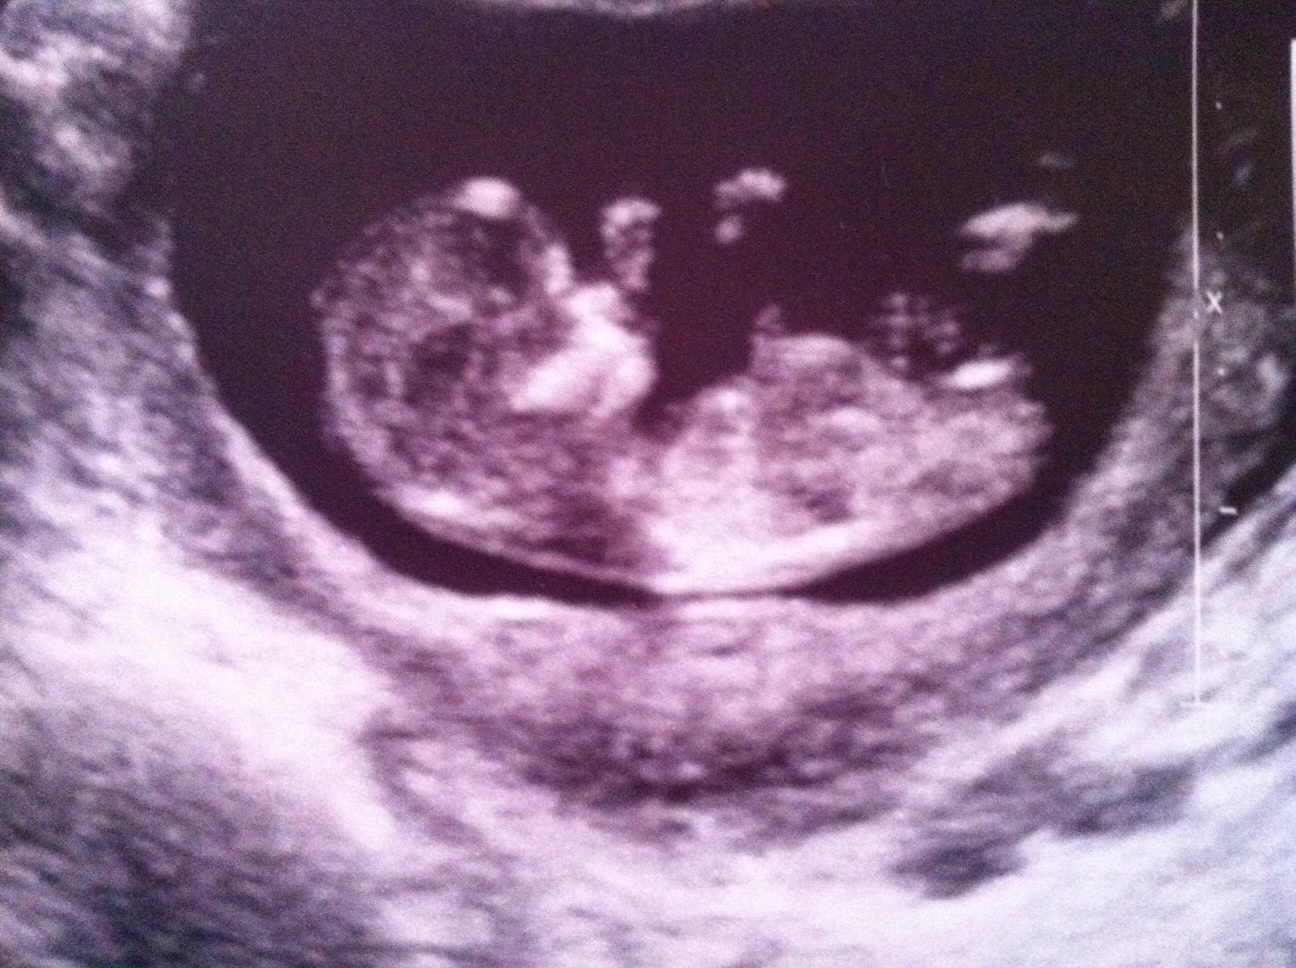

Looks girl, congrats on baby!

I think girl but worried I'm seeing what I want :)

Maybe girl

I say girl, congrats either way! x

girl guess from me :)

Update: girl! Confirmed at 2 ultrasounds and 2 different technicians at 19 and 21 weeks :)